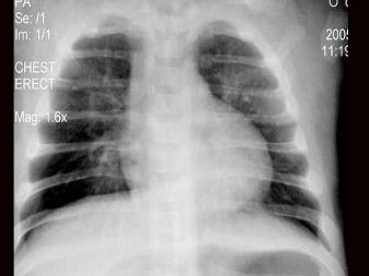

17、单项选择题

女,6岁半,咳嗽发热3天,体温39℃,胸片如图,最可能的诊断是()

A.右肺细菌性炎症

B.右肺结核

C.右侧胸腔积液

D.右肺脓肿

E.右下肺不张